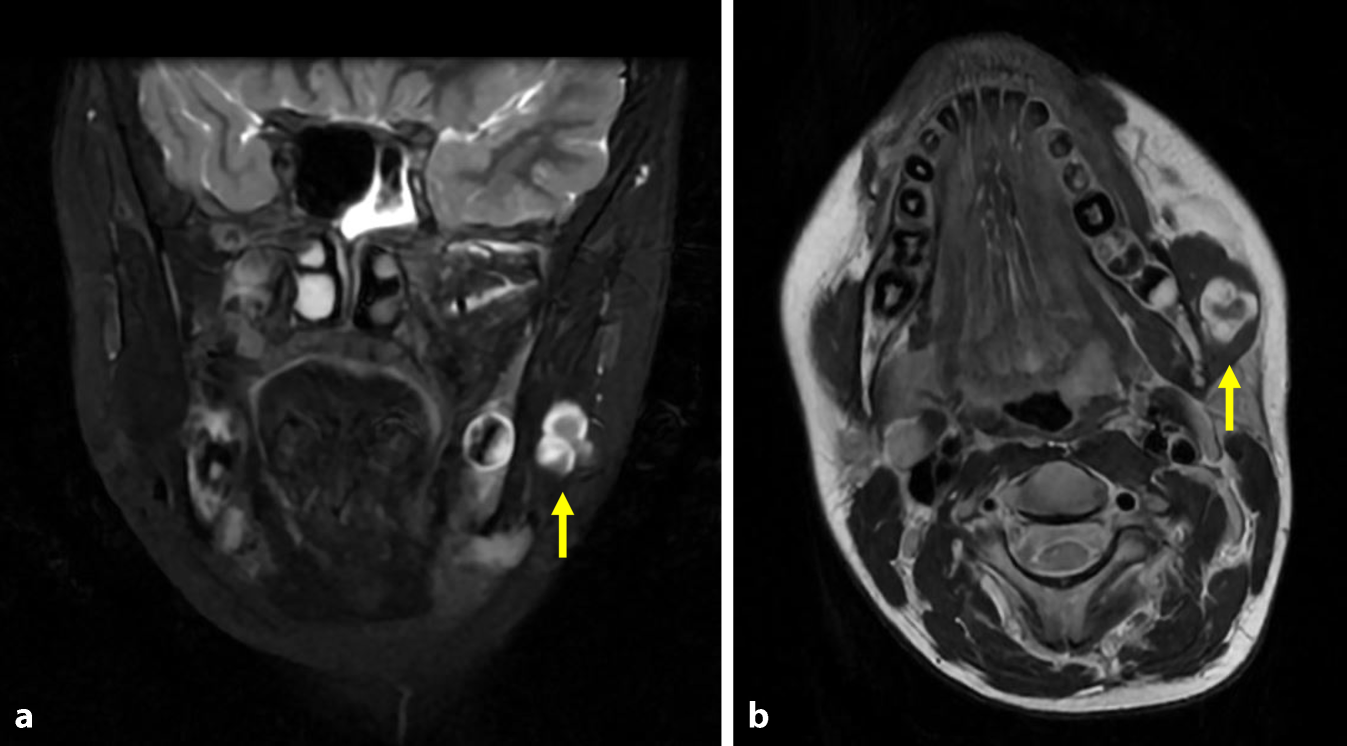

Eine darauffolgende MRT-Bildgebung des Kopf-Hals-Bereichs zeigte eine im Seitenvergleich prominente, zystisch imponierende Struktur im M. masseter links. In T2-Wichtung waren hypointense Binnenstrukturen erkennbar (Abb. 1). Zusätzlich zeigten sich vergrößerte Lymphknoten ohne Hinweise auf Abszedierung oder Einschmelzung. Seitens der Kollegen der Radiologie wurde eine sonographische Korrelation empfohlen.

Abb. 1

Natives Kopf-Hals-Magnetresonanztomogramm der Patientin in a koronarer Schichtung (STIR T2 frFSE) und b axialer Schichtung (T2 FSE). Deutlich erkennbar ist die hyperintense Raumforderung (Pfeil). STIR „short tau inversion recovery“, frFSE „fast relaxation fast spin echo“, FSE „fast spin echo“